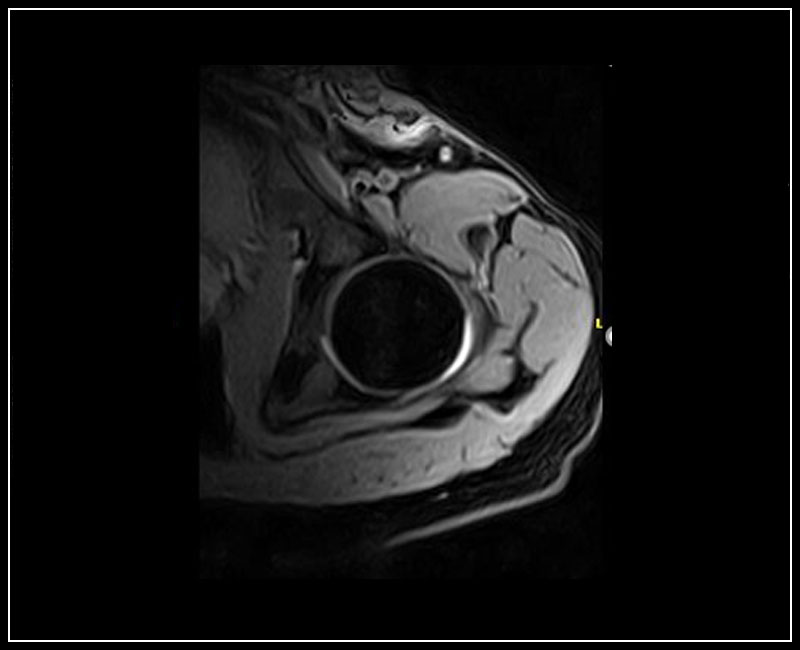

Klinické snímky